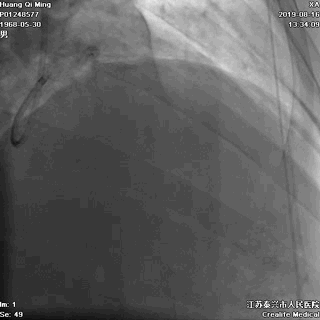

术后即刻效果满意

LAD中远段血管偏细,弥漫性病变,狭窄达90%